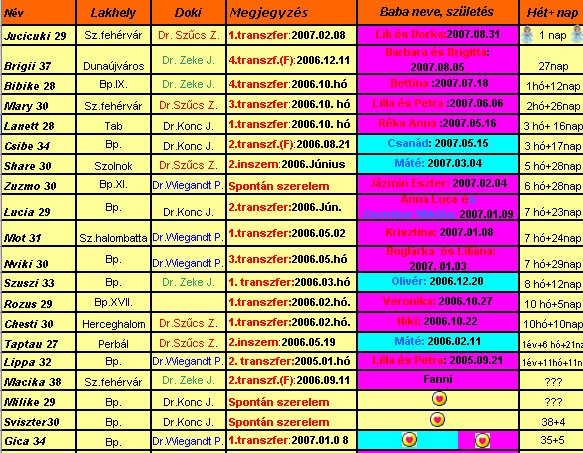

No, az új adatokat beírtam a táblába, már csak sorba rakok mindenkit, és dobok egyet!